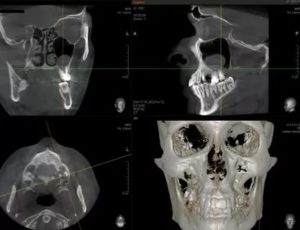

- рентгенография черепа и придаточных пазух,

- компьютерная томография.

В ходе исследования врач получает послойный срез черепа. Томография помогает выявить новообразование, определить его размеры и точную локализацию. Данное исследование позволяет оценить анатомические особенности пазухи, что очень важно для последующего хирургического лечения. Наиболее доступным методом диагностики кисты является рентгенография.

Диагностика при подозрении на кисту гайморовой пазухи – это изучение жалоб пациента, первых симптомов, признаков осложнений. Проводится риноскопия, рентген и гайморография с внедрением контрастного компонента. Дополнить диагностику могут:

- компьютерная томография;

Установить точный диагноз можно на основании рентгеновских снимков, сделанных по направлению ЛОРа или стоматолога, например, если требуется синус лифтинг. Также в диагностике используются:

- КТ (наиболее информативный метод, дающий информацию о величине, структуре и толщине стенок образования).